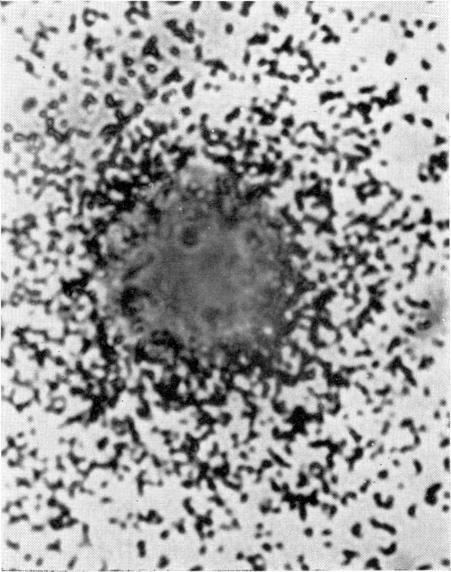

A technique is described for the detection of immunoglobulins secreted by individual lymphoid cells. Cells were cultured in agarose gel containing dilute radiolabelled anti-immunoglobulin antibodies. The secreted immunoglobulins produced a precipitin lattice which was made visible by washing the gel, followed by autoradiography. Immunoglobulin secreting cells were surrounded by clusters, or `galaxies' of silver grains. Galaxies did not appear in the presence of certain metabolic inhibitors, indicating that the secretion of immunoglobulin was an active process dependent upon cell metabolism.

本文描述了一种检测单个淋巴细胞分泌的免疫球蛋白的技术。细胞在含有稀释放射性标记抗免疫球蛋白抗体的琼脂糖凝胶中培养。分泌的免疫球蛋白形成沉淀素晶格,通过洗涤凝胶,然后进行放射自显影使其可见。分泌免疫球蛋白的细胞被银颗粒簇或“星系”包围。在某些代谢抑制剂存在的情况下,“星系”不会出现,这表明免疫球蛋白的分泌是一个依赖于细胞代谢的活跃过程。